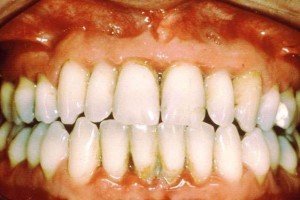

Jinjivit, so the people faced through life more known among people with gingivitis at least once in the fact that the name is important, but some people don't care that is a problem. Over time, our teeth accumulate plaque that irritate the gums and gum tissues on the outer surface of softening, swelling and reddening as the cause, the slightest bit of pressure on the gums, causing the bleeding.

Jinjivit, an easy condition to diagnose, usually when brushing your teeth bleeding gums and swelling. That doesn't cause pain that is often overlooked by people this condition is left untreated, the time to reach the bones and tissues more proficiently and scroll down, and can lead to a lot. This condition of the teeth and tooth loss leading up to and degradation separated from the meat creates a problem.